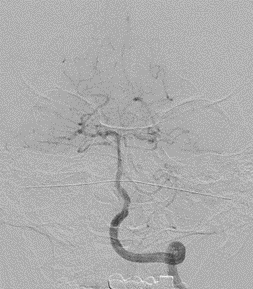

脑血管造影提示右侧颈内动脉颅内段多发动脉瘤(反主动脉弓)

脑血管造影提示右侧颈内动脉颅内段多发动脉瘤

4mm×30mm Streamline

术后4月余随访:多发动脉瘤均未见显影,远端残余轻度狭窄

术前术后对比